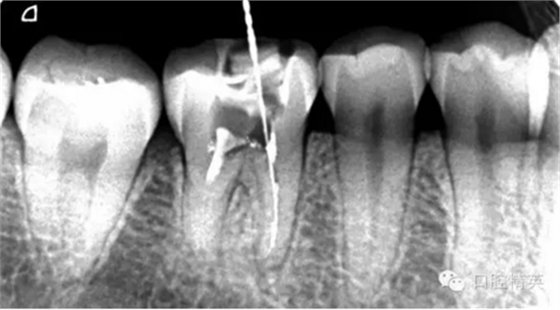

這個(gè)病例難以疏通在于根中上段堵塞,根尖下段有臺(tái)階的形成,感覺不到彎曲的方向。首先我們處理根上段,我們可以采取的方法是先預(yù)備跟中上段,將它擴(kuò)開來(lái),這樣有利于根尖下段的預(yù)備,建立良好的視野。對(duì)于根尖下段的臺(tái)階和彎曲 ,8號(hào)挫預(yù)彎,第二步要知道根管彎曲的方向,沿著根管彎曲的方向疏通。特別是有臺(tái)階的地方,一定不要硬來(lái),慢慢旋轉(zhuǎn)找到根管彎曲的方向(結(jié)合x線片)避開臺(tái)階,一定要記住慢慢旋轉(zhuǎn)角度越小越好,正旋逆旋找“緊點(diǎn)”,有經(jīng)驗(yàn)的醫(yī)生大概都知道,找到了“緊點(diǎn)”就等于找到了希望。手法一定要輕柔不易暴力!切記切記!戒浮戒躁(這句話也是特別要告訴我自己)。

近頰為疏通。慢慢找點(diǎn)可下,近頰花費(fèi)一小時(shí)。

近中兩根試尖,預(yù)備根管15分鐘。